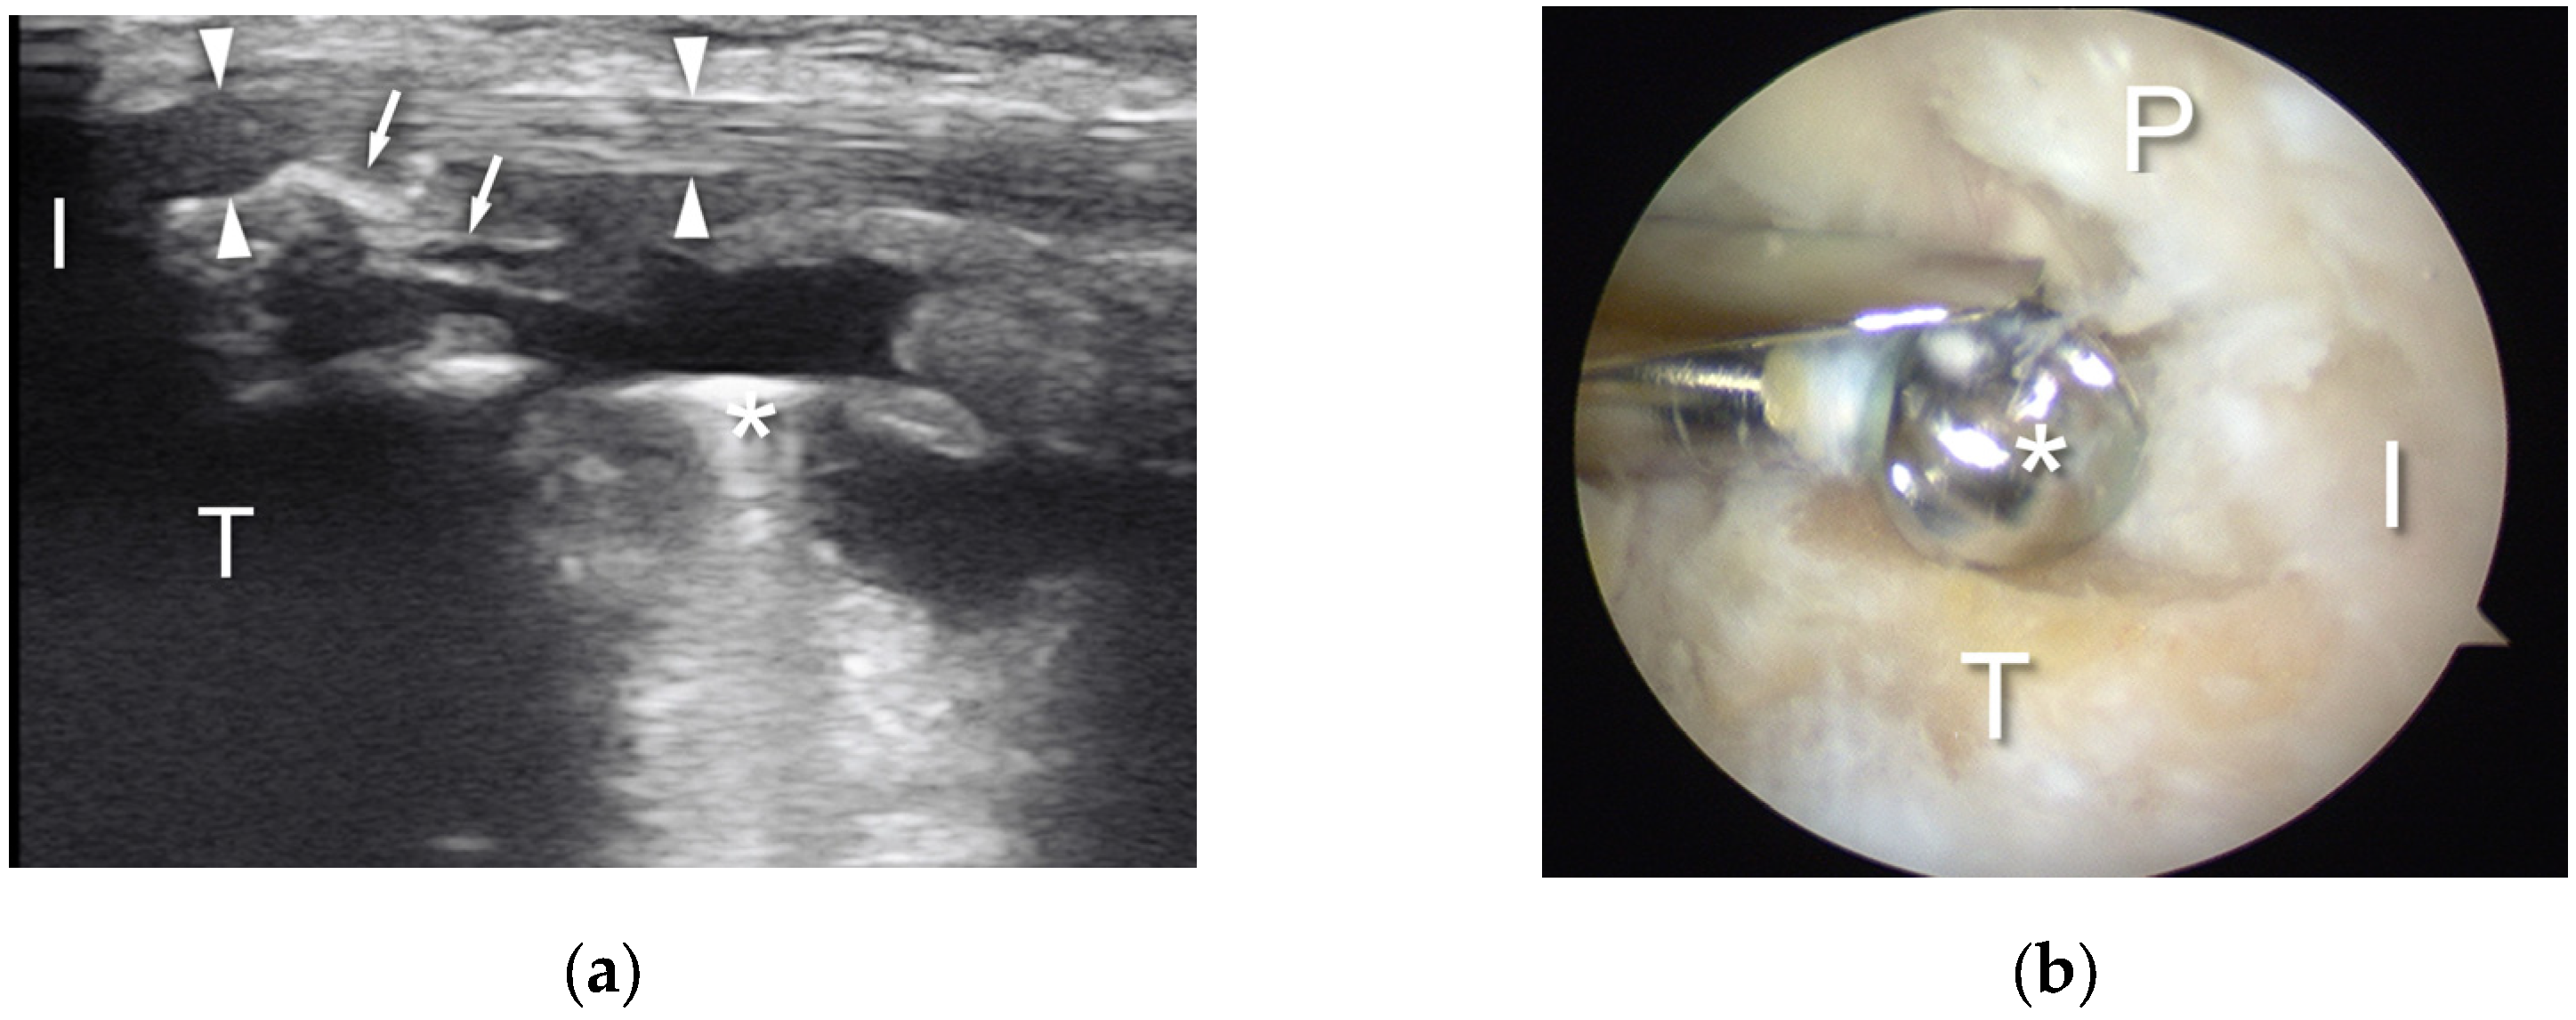

- Akatsu, Y.; Akagi, R.; Fukawa, T.; Yamaguchi, S.; Sasho, T. Ultrasound for Treating Meniscocapsular Separation Together With Arthroscopy. Arthrosc. Tech. 2016, 5, e1457–e1460. [Google Scholar] [CrossRef][Green Version]

- Paczesny, L.; Kruczyński, J. Ultrasound-Guided Arthroscopic Management of Hallux Rigidus. Videosurgery Other Miniinvasive Tech. 2016, 3, 144–148. [Google Scholar] [CrossRef]